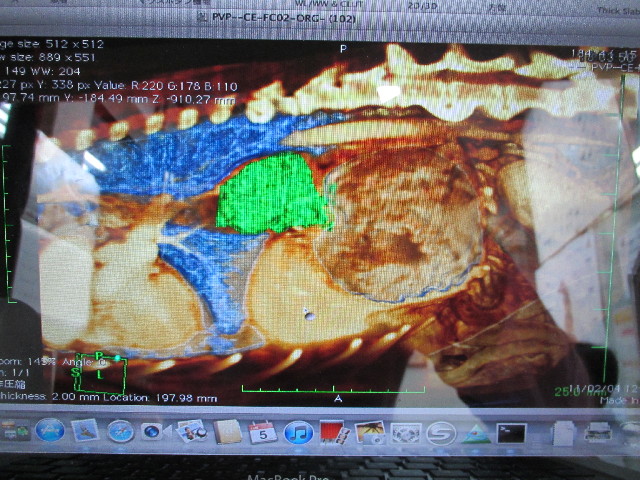

●食道の腫瘍のレントゲン

+のポンターのある、大きな風船状のものがべべちゃんの食道の腫瘍です。

これは、食道に腫瘍があることがわかった2011年2月4日に日本大学動物病院でMRI検査をしたものに着色した画像。

緑色の部分がべべちゃんの食道の腫瘍です。